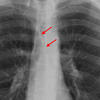

Anterior junction line